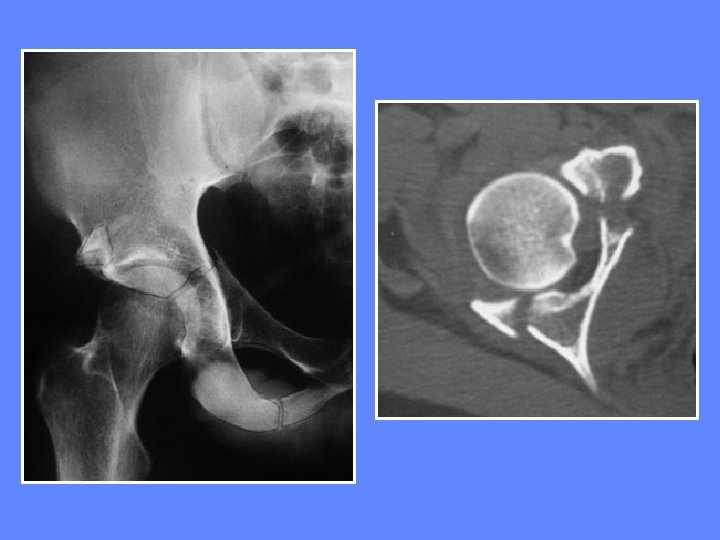

Fractures de la paroi postérieure Elles sont les plus fréquentes accompagnent en général une luxation postérieure de la hanche

Fractures de la paroi postérieure luxation postérieure de la hanche

TDM luxation postérieure de la hanche